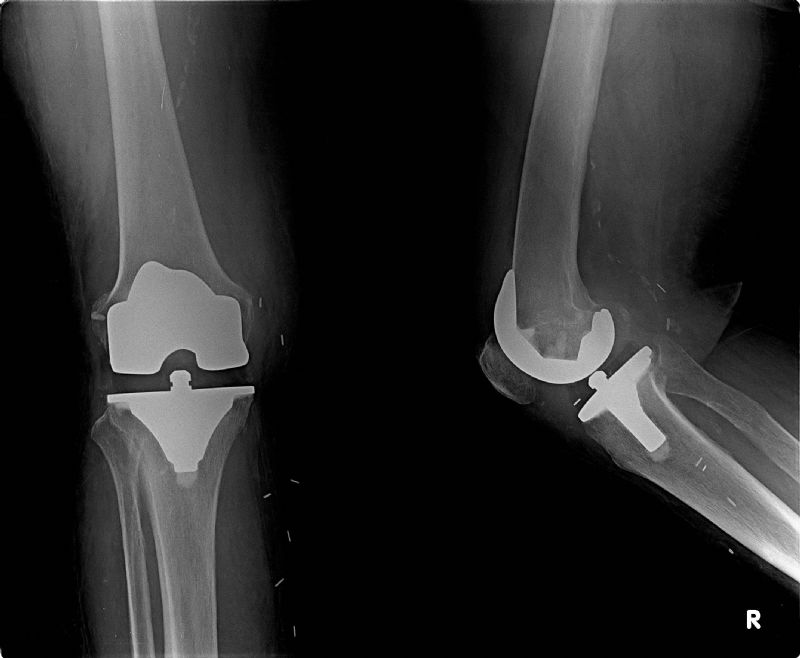

Total Diz Protezi

Total Diz Protezi Örnek Olgular

Eylül 3, 2014